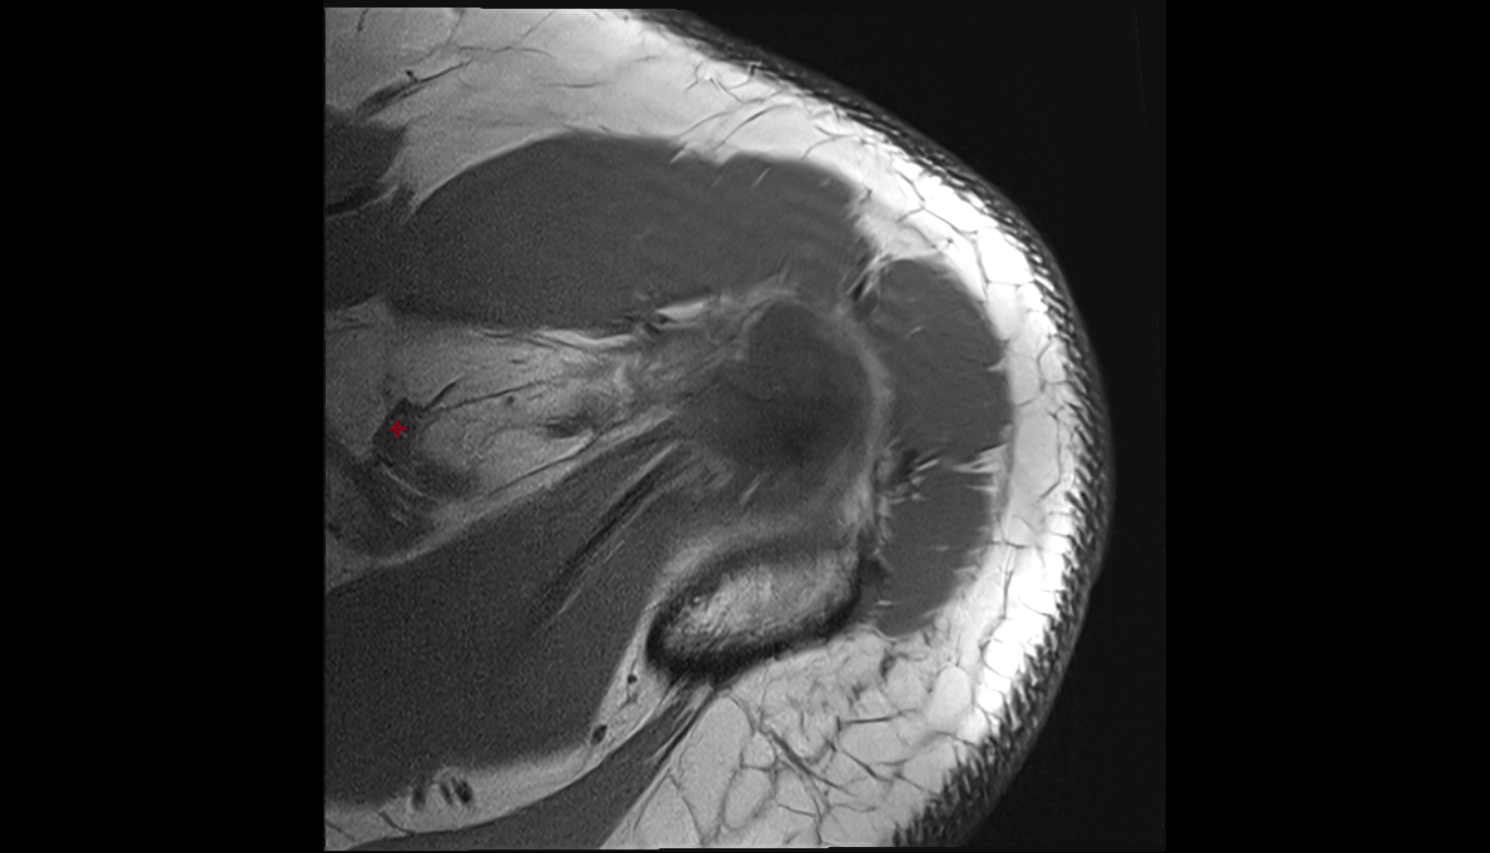

- Deltoid muscle

- Scapular spinal part of deltoid muscle

- Clavicular part of deltoid muscle

- Acromial part of deltoid muscle

- Supraspinatus tendon

- Infraspinatus tendon

- Subscapularis tendon

- Lesser tubercle of humerus

- Greater tubercle of humerus

- Head of humerus